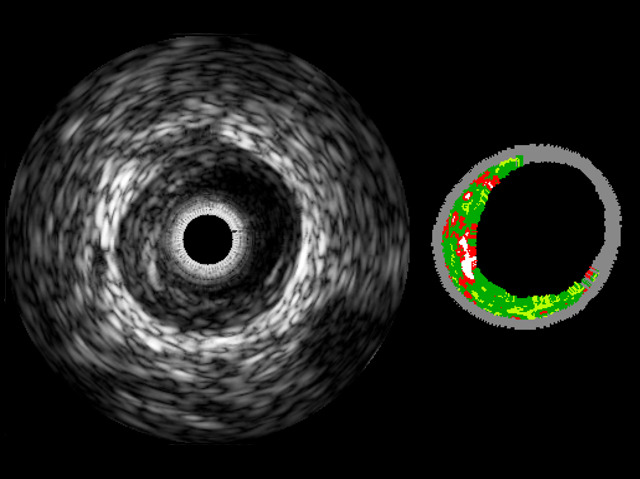

Angina is one of the most common heart conditions, affecting more than one in a hundred people. Usually limited to pain in the heart muscles, having angina can also be a sign that fibroatheromas are forming – irregularities in the walls of the vital arteries that feed the heart with oxygen. They can cause potentially life threatening blood clots and are notoriously hard to detect because they form inside the walls of the arteries, so outwardly arteries can appear clear and healthy. Ultrasound – the same technology used to see babies in the womb – can provide a view into the artery wall (left). By transforming this image into a computer generated 'virtual' artery, fibroatheromas can be pinpointed (right – shown in white). Scientists are now looking for the proteins responsible and may already have found one.